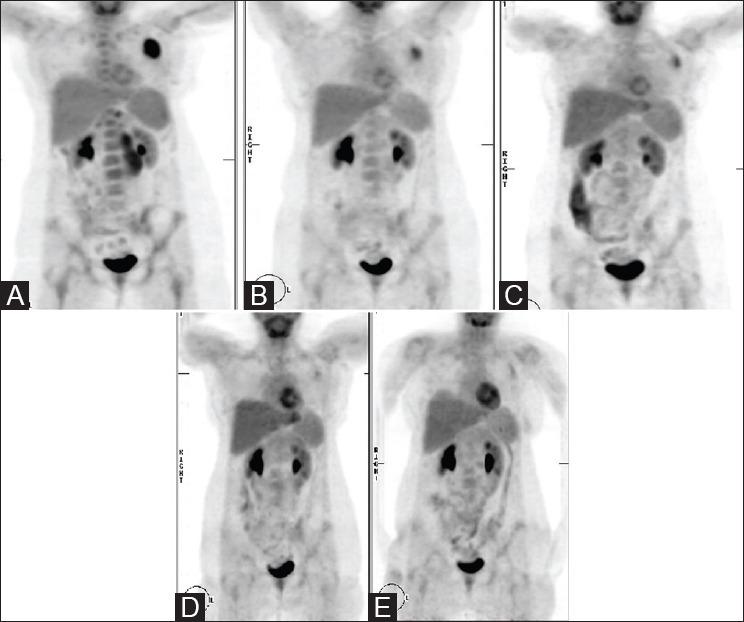

Radioimmunotherapy (RIT) has been available for some time to treat patients with non-Hodgkin's lymphoma, but its use in Hodgkin's lymphoma has been less available, partly because of the need to find an appropriate antibody. A new radioiodinated chimeric antibody directed against the CD25 epitope (I basiliximab) seems promising, but assessment of response has been difficult. F-fluorodeoxyglucose-positron emission tomography (F-FDG-PET) has become a standard method by which the response of Hodgkin's disease to chemotherapy is both predicted and assessed with well-understood criteria of response. The aim of this study is to determine F-FDG-PET can be used to assess response to RIT. Pre- and post-treatment F-FDG-PET imaging was performed in a series of 13 patients with advanced Hodgkin's disease who had failed conventional therapy and had been enrolled on a compassionate use program for treatment with I basiliximab. The I basiliximab was given at an activity of 1200MBq/m with one patient receiving 2 cycles and the rest a single cycle. The F-FDG-PET studies were compared using the "Deauville" criteria and by comparing the maximum standardized uptake value (SUVmax) of target tumors before and 4 and 8 weeks after treatment. All patients survived long enough for their initial F-FDG-PET-computed tomography scan at 4 weeks after their I basiliximab therapy. One out of ten patients with "Deauville" Grade 4 or 5 response died during the 6-month follow-up period. Two out of three patients with a "Deauville" Grade 2 or 3 response died in the follow-up period. The mean SUVmax pretreatment was 11.9 (±4.7); at 4-week posttreatment, the mean SUVmax was significantly lower at 6.5 (±5.8) ( = 0.02). At 8 weeks, the mean SUVmax was 8.8 (±7.0), which was not significantly different from the pretreatment level. F-FDG-PET imaging is able to predict the short-term response to treatment of Hodgkin's disease by RIT, and an initial poor response appears to predict poor outcome. Early changes in F-FDG-PET uptake did not predict sustained response and by 8 weeks all but one patient had recurrent disease.

放射免疫疗法(RIT)已应用于治疗非霍奇金淋巴瘤患者一段时间,但在霍奇金淋巴瘤中的应用较少,部分原因是需要找到合适的抗体。一种针对CD25表位的新型放射性碘化嵌合抗体(碘巴利昔单抗)似乎很有前景,但评估反应一直很困难。氟脱氧葡萄糖正电子发射断层扫描(F-FDG-PET)已成为一种标准方法,可根据已明确的反应标准来预测和评估霍奇金病对化疗的反应。本研究的目的是确定F-FDG-PET是否可用于评估对RIT的反应。对13例晚期霍奇金病患者进行了治疗前和治疗后的F-FDG-PET成像,这些患者常规治疗失败并参加了一项使用碘巴利昔单抗的同情用药项目。碘巴利昔单抗的给药活度为1200MBq/m²,1例患者接受2个周期治疗,其余患者接受1个周期治疗。使用“多维尔”标准并通过比较治疗前、治疗后4周和8周时靶肿瘤的最大标准化摄取值(SUVmax)来比较F-FDG-PET研究结果。所有患者在接受碘巴利昔单抗治疗后4周存活时间足够长,可进行首次F-FDG-PET计算机断层扫描。在6个月的随访期内,10例“多维尔”4级或5级反应患者中有1例死亡。3例“多维尔”2级或3级反应患者中有2例在随访期内死亡。治疗前SUVmax的平均值为11.9(±4.7);治疗后4周,SUVmax的平均值显著降低至6.5(±5.8)(P = 0.02)。在8周时,SUVmax的平均值为8.8(±7.0),与治疗前水平无显著差异。F-FDG-PET成像能够预测RIT治疗霍奇金病的短期反应,初始反应不佳似乎预示着预后不良。F-FDG-PET摄取的早期变化并不能预测持续反应,到8周时,除1例患者外,所有患者均复发。